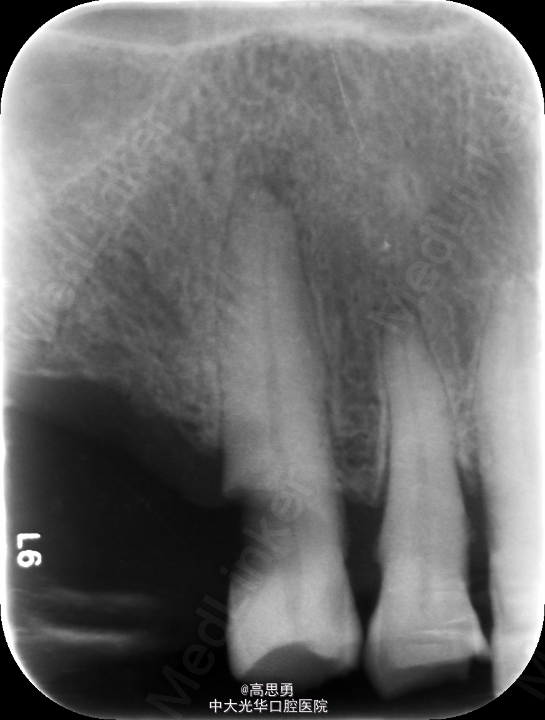

根尖X片示:13 根尖部阴影,牙颈部硬组织部分缺损

13 探(-)、叩(-)、松(-),HE面见白色暂封物

根尖X片示:13 根尖部阴影,根充可

1、临床检查和#13树脂充填 对患者进行全面的口腔检查,用Z350树脂充填#13,调HE,抛光。